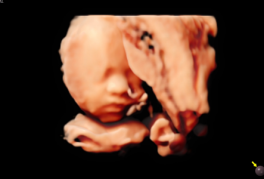

RealisticVue™ proporciona un renderizado 3D con detalle anatómico realista y percepción de profundidad, permitiendo visualizar rostros fetales y estructuras críticas con claridad. Esta función es ideal para seguimiento de desarrollo fetal y estudios de anatomía detallada, ofreciendo a los especialistas herramientas confiables para la evaluación prenatal.